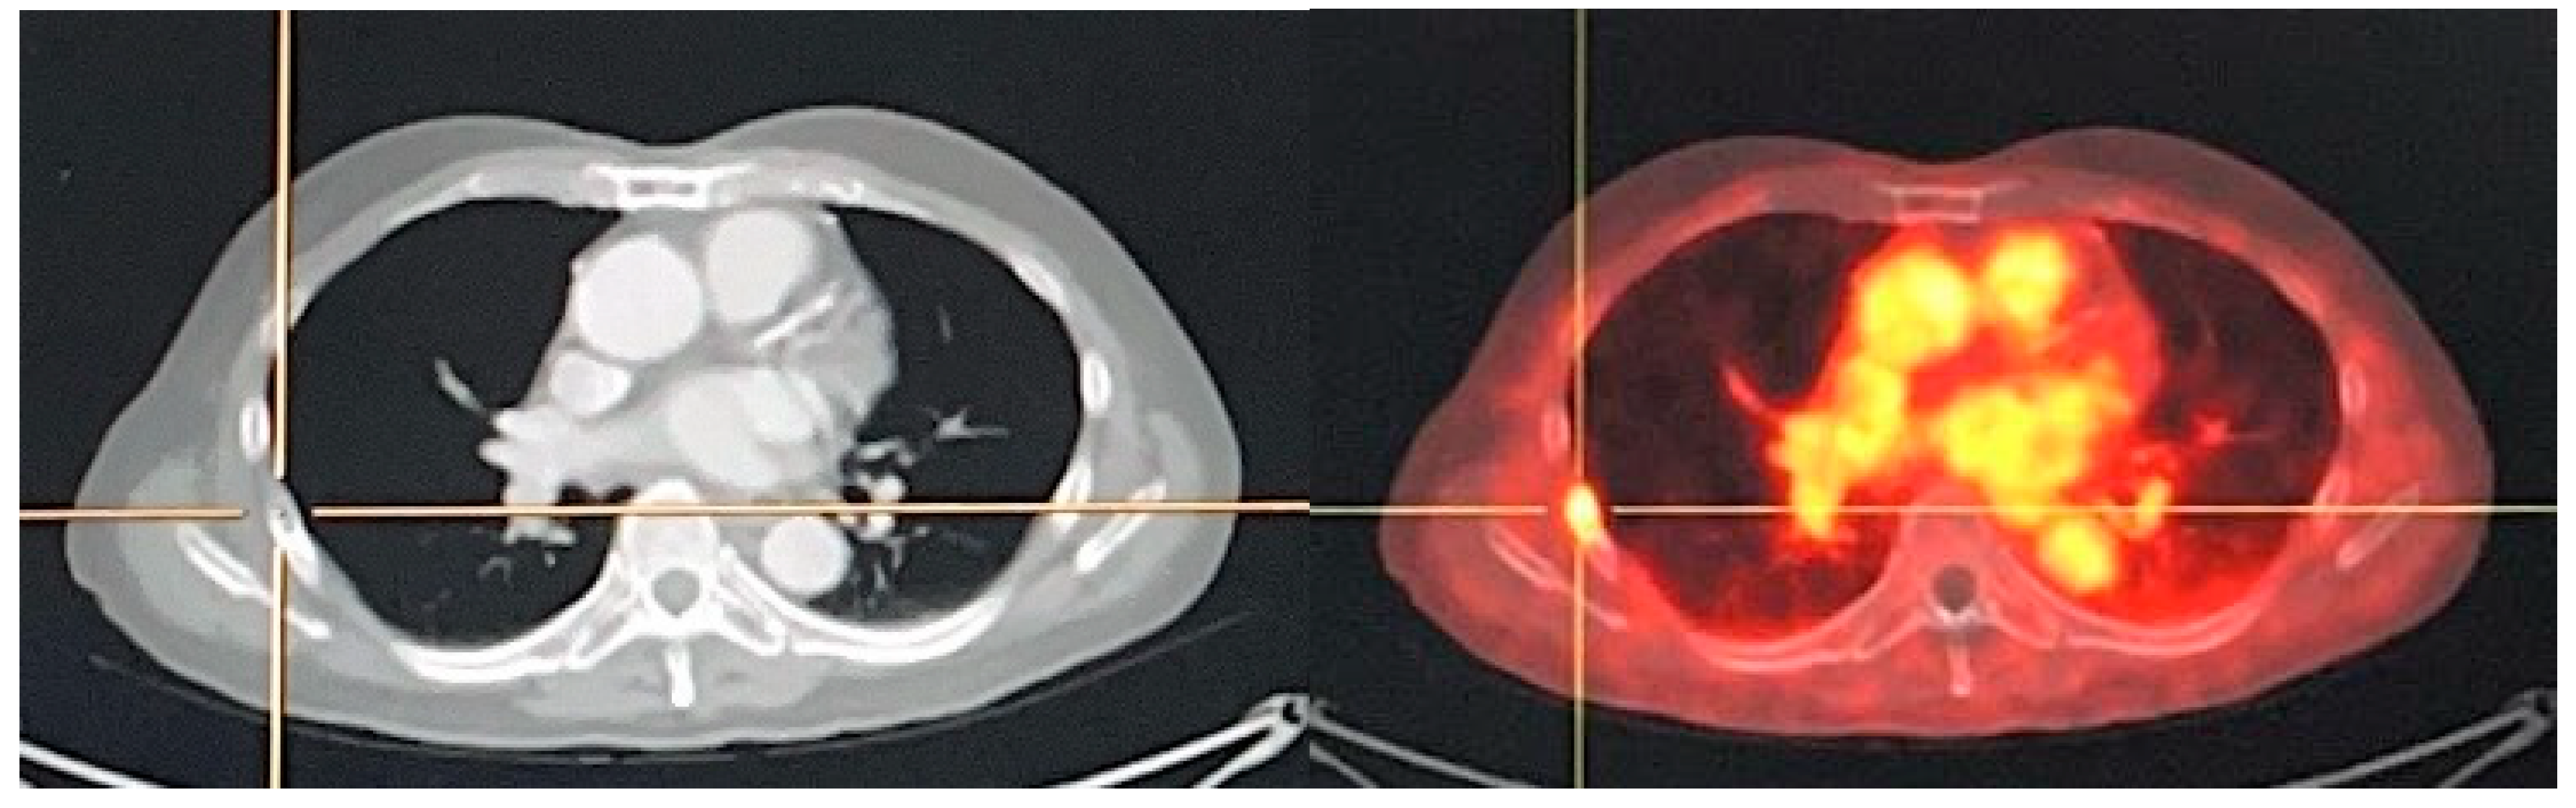

Figure 5.

A 75-year-old man with diagnosed PCa (Gleason score of 4 + 4, initial PSA of 43.12 ng/mL) who underwent 18F-PSMA PET/CT for initial staging. PET/CT scan reveals PSMA uptake at prostatic bed with multiple osteoblastic metastases at vertebrae. There are few subcentimeter mild PSMA-avid nodes at right lower paratracheal regions (SUVmax of 2.72) which are suspected of reactive nodes (A). Transaxial PET/CT in lung window (B) revealed increased PSMA uptake associated with reticulonodular infiltration at RUL which was suspected of pulmonary infection. After follow-up imaging, pulmonary lesion was improved, and mediastinal nodes revealed no significant change in size but no longer observable PSMA uptake.